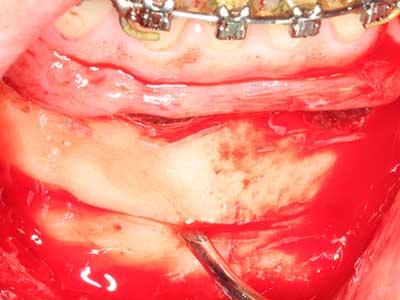

Фиг. 18: Препарация на кортикално покритие с пиезо накрайник за кост (Piezomed, W&H).

Фиг. 19: Хирургичното поле след невролиза и отстраняване на остеотом.

Фиг. 20: Отстраненото костно покритие е поставен отново и фиксиран с винт за остеосинтеза (KLS Martin, Tuttlingen).